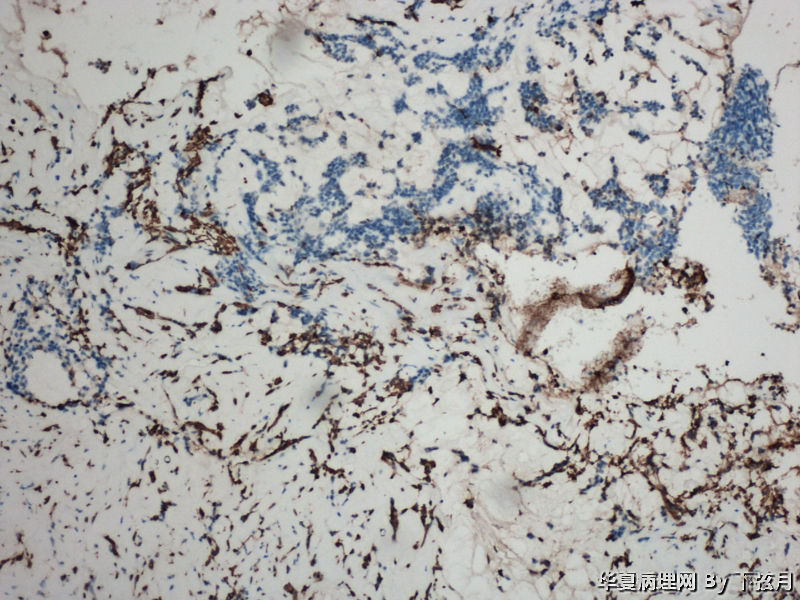

描述:GFAP 100倍

左侧颞叶及胼胝体膝部占位图13

名称:图13

描述:GFAP 200倍

考虑黏液型乳头状室管膜瘤

丰富黏液背景,漂浮乳头状或簇状分布的瘤细胞,免疫组化GFAP,S-100阳性。

This enhancing lesion with GFAP positive cells and should consider some type of glioma, probably high-grade.

But some cells in fig 7 and 8 are worrisome, need to rule out other type tumors, like chordoma. Other small round blue cell tumors.